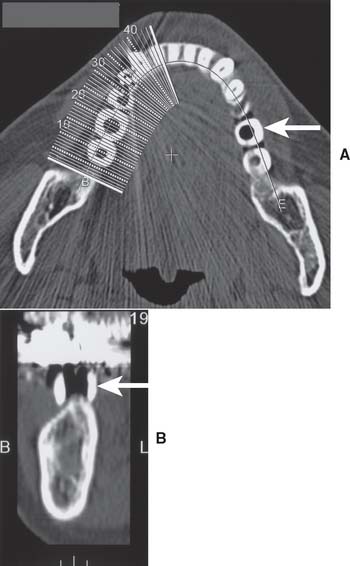

The widths of the posterior mandible and maxilla are determined primarily by clinical examination. Bone width not revealed on a panoramic film can be evaluated in the anterior maxilla and mandible with a cephalometric film (Fig. 13-7). The location of the inferior alveolar canal and maxillary sinus can be determined by specialized computed tomography (CT) scans (Fig. 13-8), although high radiation exposure and considerable expense may limit their routine use. However, significant advances being made in this technology may change this trend.

A clear resin facial veneer template is recommended for anterior implant placement to allow the surgeon access to the osseous receptor site and an unimpeded view of the frontal and sagittal angulations as the site is being prepared. This type of template is fabricated from a diagnostic waxing or denture tooth arrangement on a mounted cast. The waxing is duplicated with alginate or polyvinyl siloxane and poured in quick-setting stone. Then 1.5-mm (0.060-inch)–thick of vacuum-formed matrix material is adapted to the replicated cast. For accurate orientation, the vacuum-formed matrix should be trimmed to extend over the full facial surface of the teeth being restored and about a third of the facial surface of the remaining dentition. This template is removed from the duplicate cast and returned to the original cast. A 2-mm thickness of autopolymerizing resin is added to the lingual surface to compensate for the space occupied by the porcelain on the implant restoration (Fig. 13-20). (The total thick-ness, including an additional millimeter from the vacuum-formed matrix, is about 3.0 mm.) To make surgical guides appear radiopaque, barium powder is often added to the resin during its fabrication (see Fig. 13-8). The surgeon must stay as close as possible to this guide during implant placement, which allows maximum flexibility in selecting an implant site without violating the facial surface or forcing screw access holes to be located inappropriately in the facial surface of the restoration. Following this guide enables the surgeon to place a fixture in the best location with minimum undesirable sagittal angulation. If a cement-retained restoration is desired, the orientation of the implant can be slightly more facial.